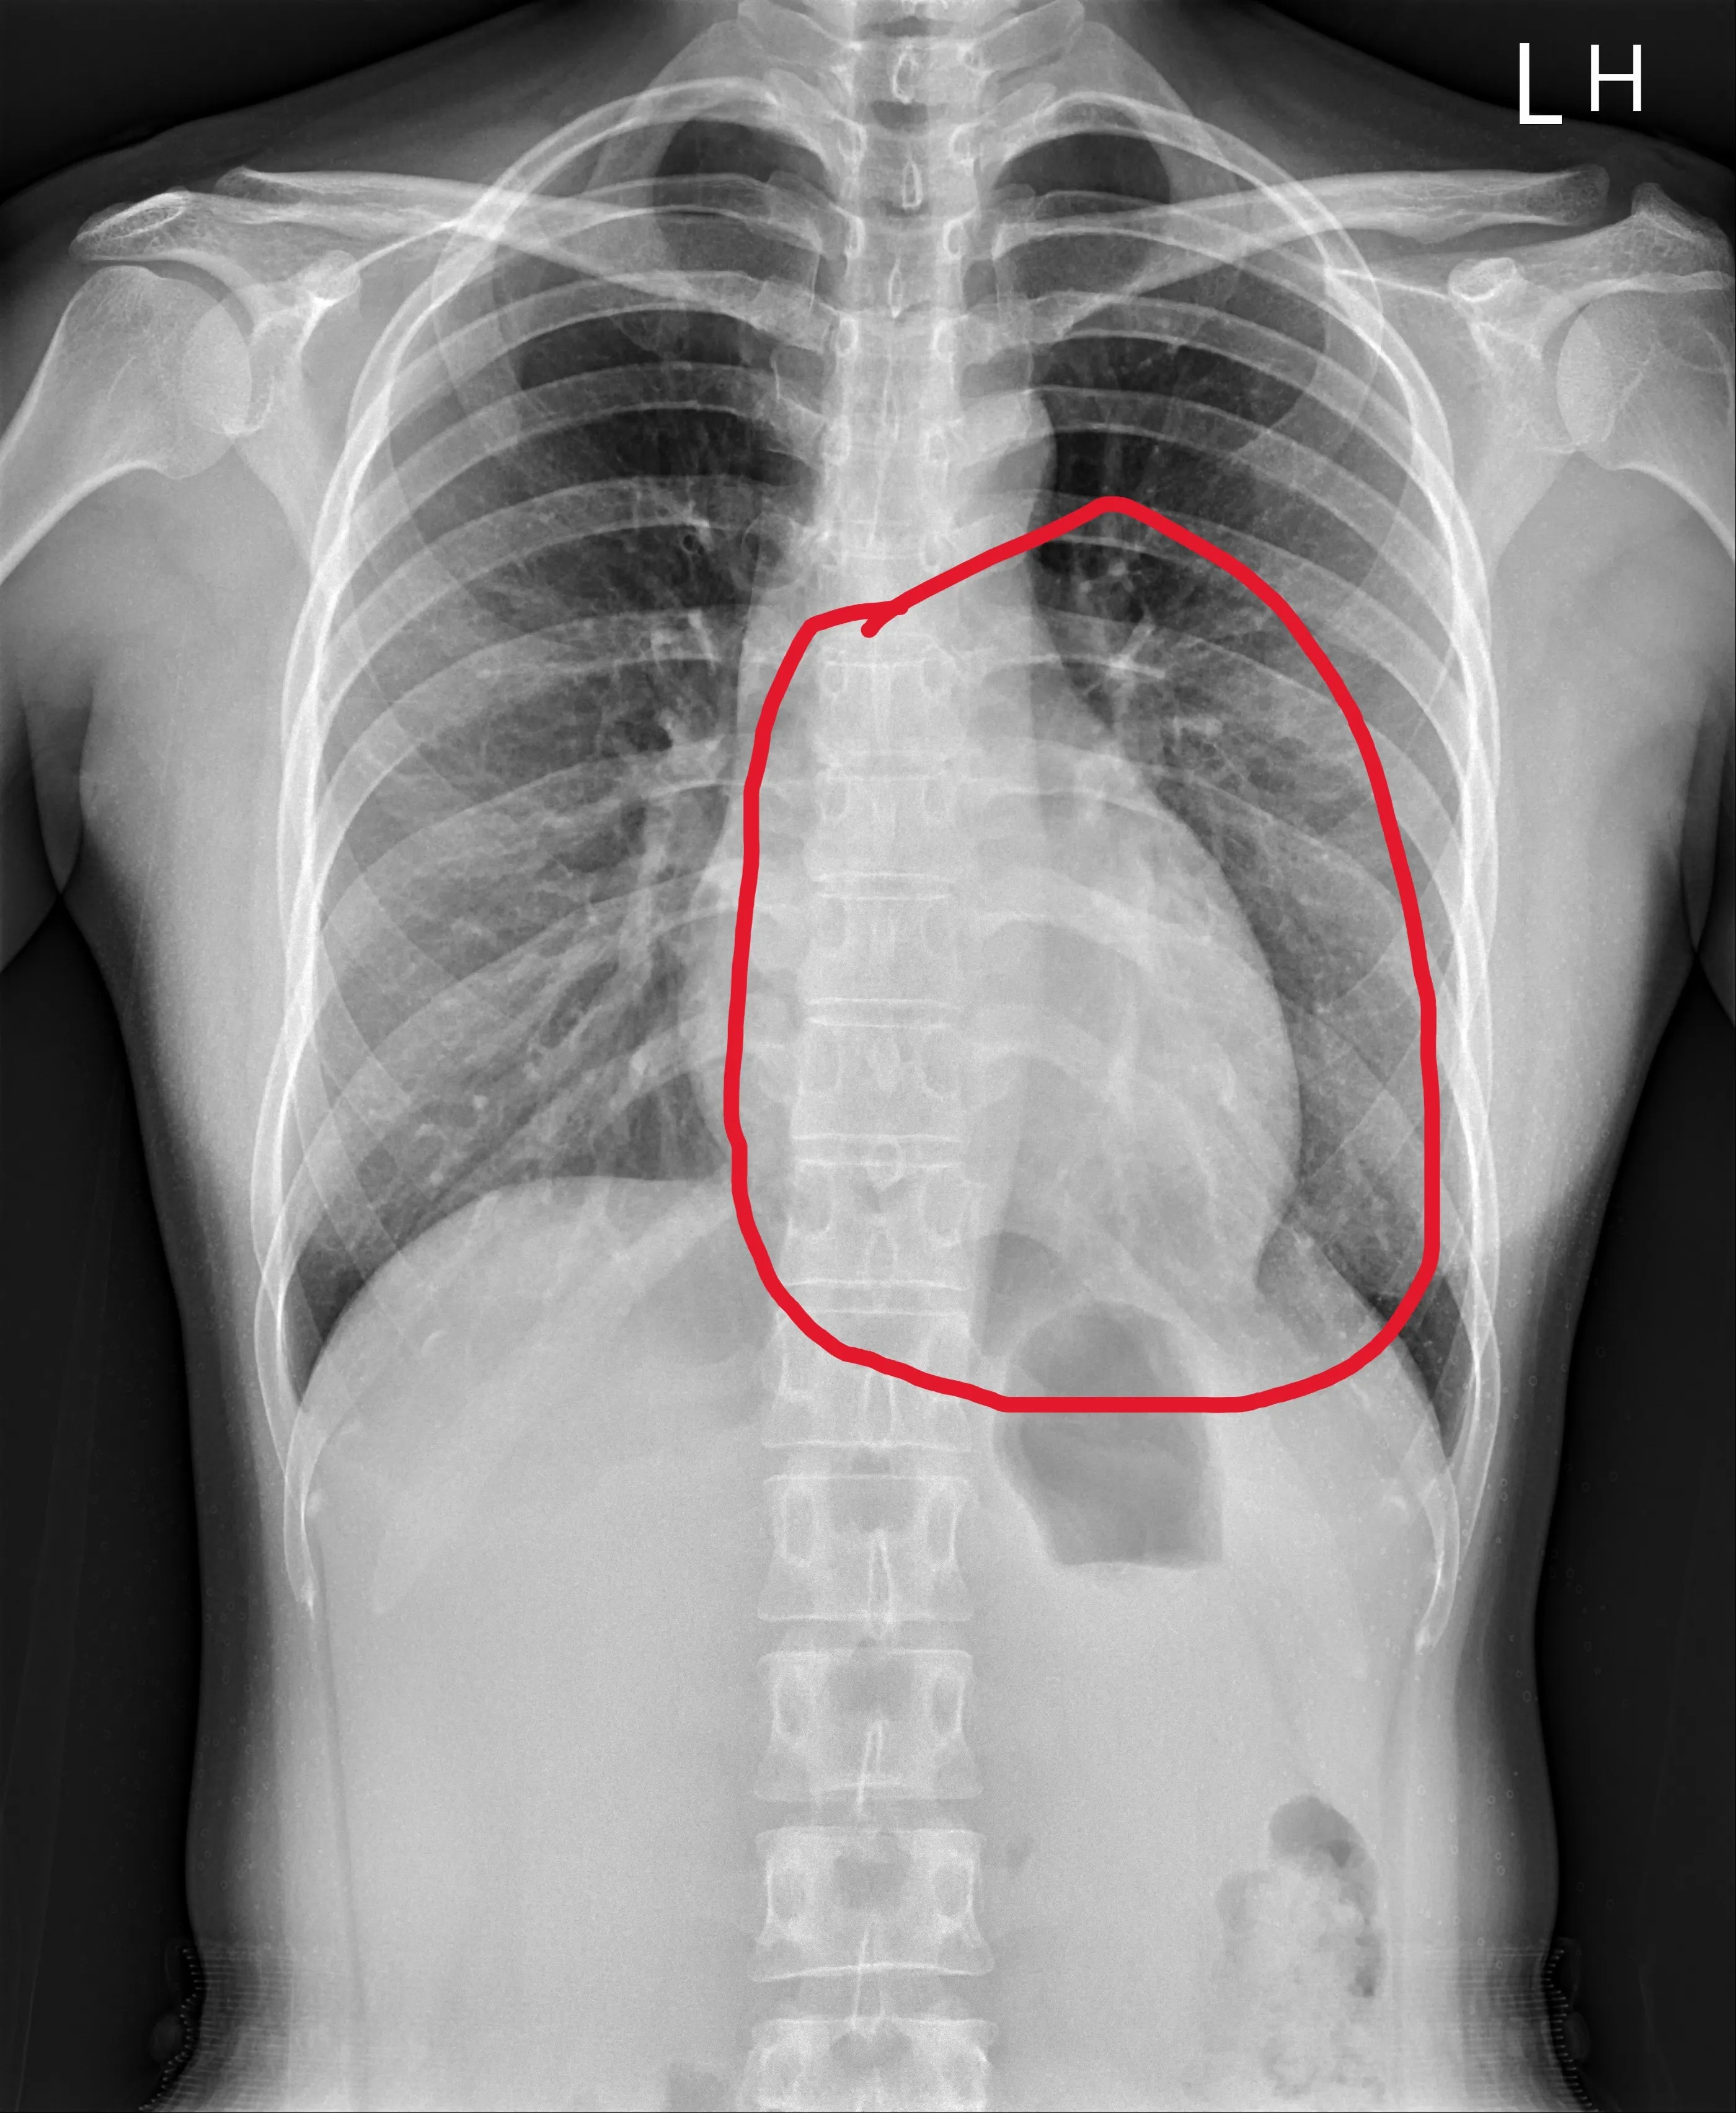

26歲患者去年7月就醫時,心臟( 紅線圈內)顯得較肥大。(員榮醫院提供)

一名26歲女子去年健檢時經由X光片發現心臟擴大,經門診就醫,發現左心室射出分率只有39%,已符合心臟衰竭定義。追查後,發現女子有甲狀腺家族病史,經按時服藥近10個月後,如今已痊癒。專家指出,除服藥外,心臟衰竭患者也能借由EECP(一種非侵入性的心血管輔助治療,又稱體外反搏治療)改善病情。

員榮醫療體系員榮醫院心臟內科主治醫師陳裕峰表示,患者就醫時並沒有喘或胸悶等典型症狀,但心臟收縮功能非常差,左心室射出分率只有39%,一般應該至少要50%以上,甚至60%以上才算正常,39%已符合心臟衰竭,心臟超音波發現瓣膜逆流比較嚴重。之後為患者制定一系列心臟衰竭標準治療,經10個月治療,心臟大小已恢復正常,左心室射出分率從原本的39%大幅進步到59%,接近正常值。